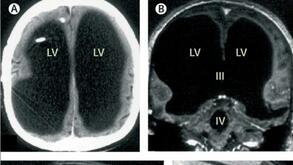

44-годишен французин посетил болница, след като усетил слабост в крака си. Лекарите направили изненадващо откритие: почти целият му мозък липсвал. Черепът му бил запълнен почти изцяло с течност, като от мозъчната тъкан бил останал само тънък слой...